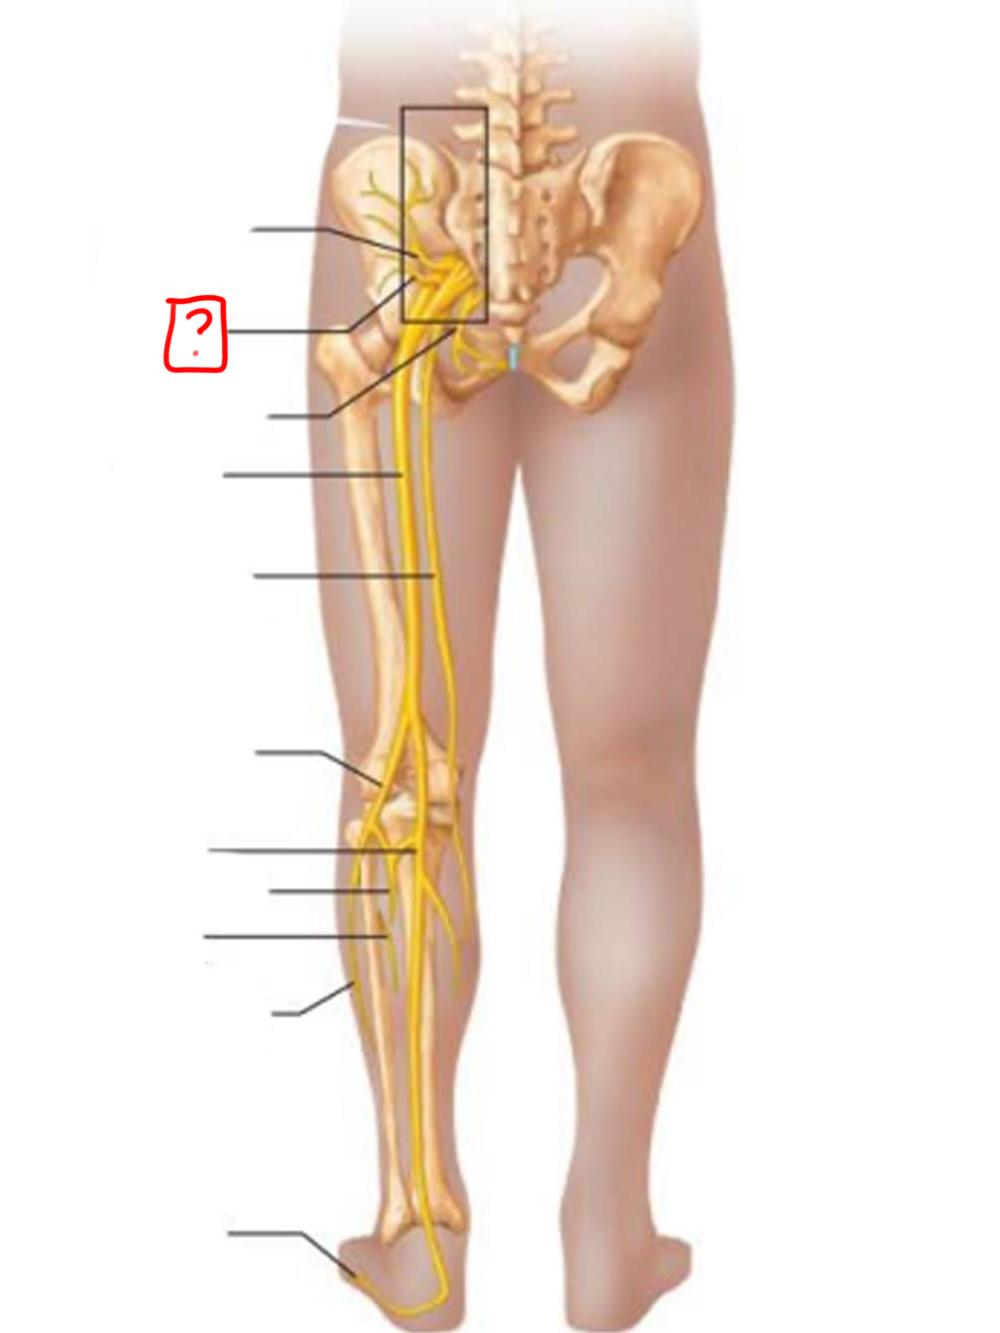

obturator

femoral

lumbosacral trunk

iliohypogastric

ilioinguinal

femoral

lateral femoral cutaneous

obturator

anterior femoral cutaneous

saphenous

superior gluteal

inferior gluteal

pudendal

sciatic

posterior femoral cutaneous

common fibular

tibial nerve

sural (cut)

deep fibular

superficial fibular

plantar branches

superior gluteal

lumbosacral trunk

inferior gluteal

common fibular

tibial

posterior femoral cutaneous